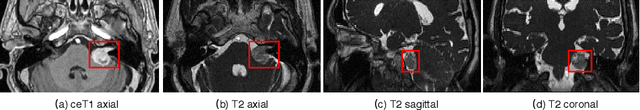

Figure 1 for Automatic Segmentation of Vestibular Schwannoma from T2-Weighted MRI by Deep Spatial Attention with Hardness-Weighted Loss